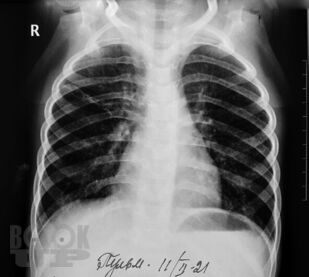

Сборник включает вызвавшие наибольший интерес аудитории лекции и доклады на различных научно-практических конференциях в 2020-2021 гг. по актуальным проблемам пульмонологии и аллергологии детского возраста, таким как: современные методы диагностики и лечения, острые и хронические инфекционно-воспалительные и аллергические заболевания органов дыхания, муковисцидоз, туберкулез органов дыхания, COVID-19, а также различные другие информационные материалы. Ежегодник адресован практикующим детским пульмонологам и аллергологам.